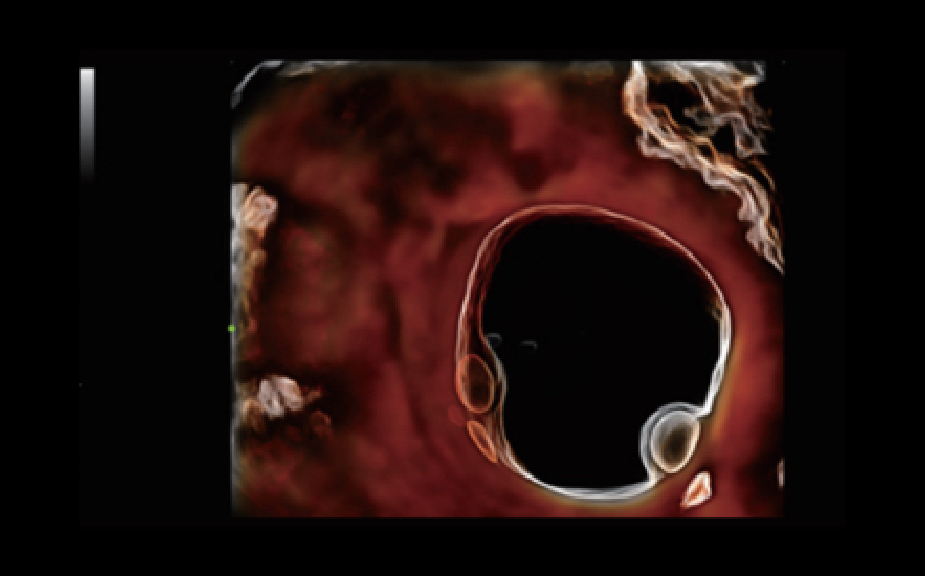

Nuewa I9, kad?nlara ve yenido?anlara y?nelik sa?l?k hizmetleri i?in ?zel olarak tasarlam??t?r ve i?ten d??a yenilik?i bir deneyim sunmaktad?r. Bu yenilikler, karma??k klinik senaryolara ili?kin derinlemesine bilgilere dayal? olarak geli?tirilmi?tir ayr?ca do?ru ve zaman?nda yan?tlar?n yan? s?ra, ola?an├╝st├╝ verimlilik ve ola?an├╝st├╝ kullan?c? deneyimi sunar.

ZST + Taraf?ndan Desteklenen Eksiksiz ??z├╝m

ZST+ platformu, ultrason evrimini temsil eden ola?an├╝st├╝ bir yeniliktir. Ultrason ?l?├╝mlerini geleneksel ???n bi?imlendirmeden kanal verilerine dayal? i?lemeye d?n├╝?t├╝r├╝r. Mekansal ??z├╝n├╝rl├╝k, zamansal ??z├╝n├╝rl├╝k ve doku homojenli?i aras?ndaki geleneksel dengeli s?n?rlaman?n ├╝stesinden gelir ve kesintisiz iyile?tirmelerle s?n?rs?z g?r├╝nt├╝leme ??z├╝mleri i?in ola?an├╝st├╝ g?r├╝nt├╝ kalitesi sunar.